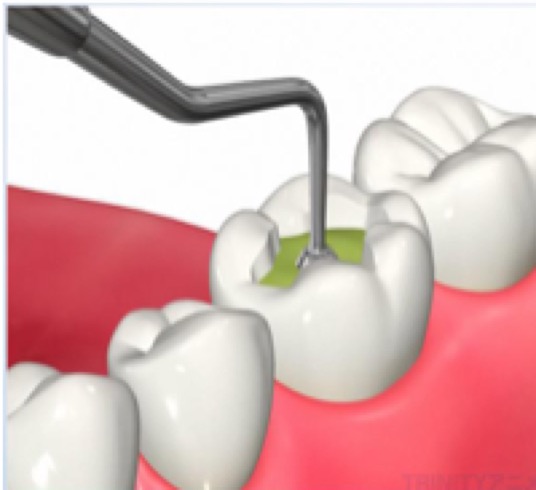

1.虫歯を削ります

虫歯を取り残さないよう、虫歯の部分のみを選択的に染め出し(う蝕検知液を使用)ながら、慎重に虫歯を取り除きます。